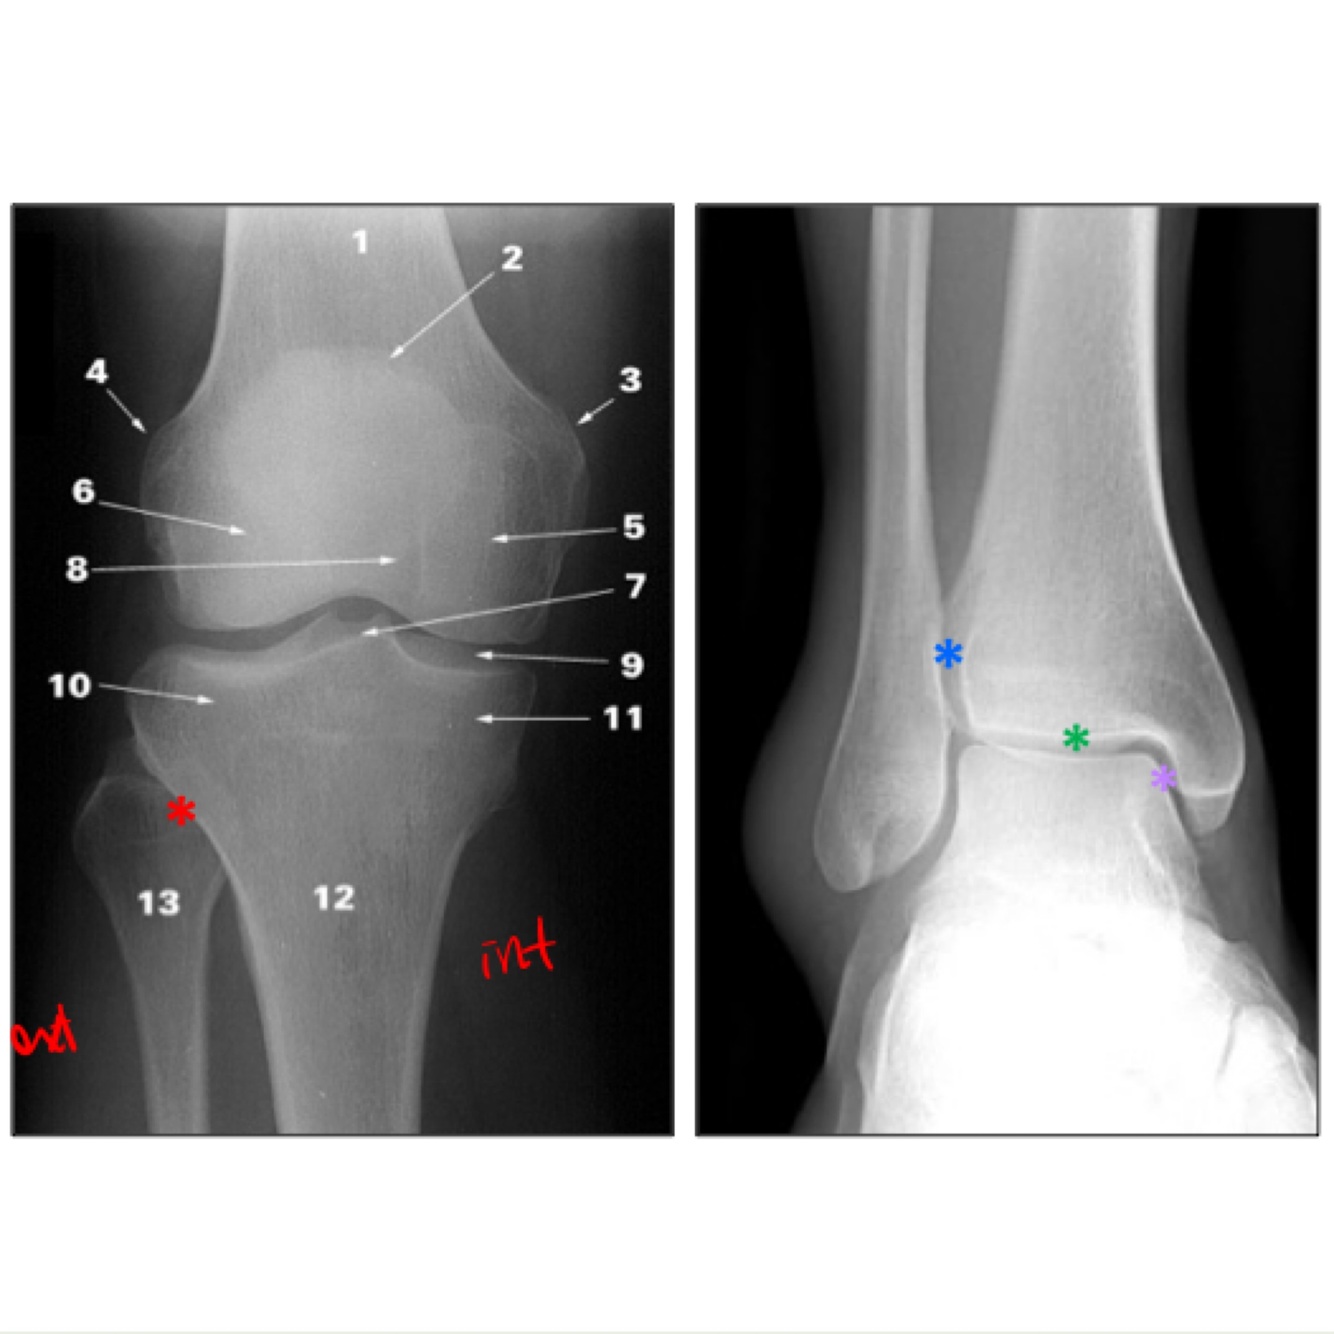

Nomme les chiffres sur l epiphyse proximale du tibia svp bibiboubobibou

les surfaces articulaires des condyles médial (1) et latéral (2) En vert: l'éminence intercondylaire. -Aire intercondylaires antérieure (7) et postérieure (8) -tubercules intercondylaires médial (5) et latéral (6) (Le médial se situe au bord latéral de la surface articulaire du condyle médial et le latéral se situe au bord médial de la surface articulaire du condyle latéral) ouin ca gosse

31

L aire intercondylaire antérieure de lepiphyse proximale du tibia (7) donne l’insertion de 2 structures…lesquelles

-Les cornes antérieures des ménisques médial et latéral du genou - ligament croisé antérieur

L aire intercondylaire postérieure (8) de l epiphyse proximale du tibia donne l insertion de deux structures

-cornes postérieures des ménisques médial et latéral du genou -ligament croisé postérieur

Quesqui s insère sur la tubérosité tibiale?

La surface articulaire fibulaire se situe sur la face ___________ du condyle _________ du tibia

La face posterolaterale du condyle lateral

Quesqui s'insère sur le relief en vert sur l'image

Il s’y insère le tractus iliotibial et quelques fibres du muscle tibial antérieur (Le relief en vert est est le tubercule du tractus iliotibial)